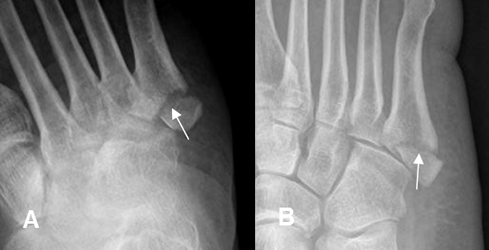

Fig 50 A. Fractura del 5º metatarsiano.

A: Rx oblicua y B: Rx lateral. Fractura transversa, lineal y no desplazada, en el tercio proximal del 5º metatarsiano.